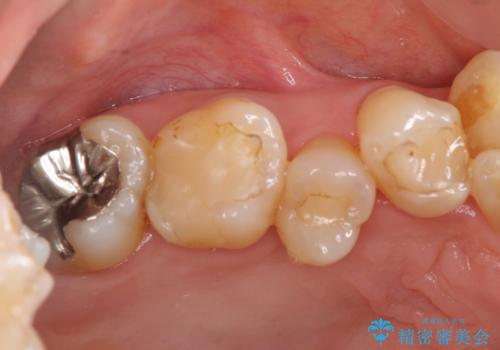

奥歯の銀歯、プラスチックのやりかえ

- 奥歯の詰め物のやり替えを希望して来院。

銀歯と、プラスチックをセラミックにかえました。

古い詰め物を取るときに、しっかり虫歯はとっています。

右上6番は詰め物が大きく、インレーではなくクラウンとしました。